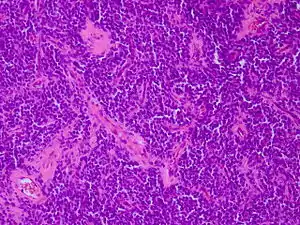

| Micrograph of an H&E stained section of a peripheral PNET. | |

Peripheral PNET

The peripheral PNET (pPNET) is now thought to be virtually identical to Ewing sarcoma:

"Current evidence indicates that both Ewing's sarcoma and PNET have a similar neural phenotype and, because they share an identical chromosome translocation, they should be viewed as the same tumor, differing only in their degree of neural differentiation. Tumors that demonstrate neural differentiation by light microscopy, immunohistochemistry, or electron microscopy have been traditionally labeled PNETs, and those that are undifferentiated by these analyses have been diagnosed as Ewing's sarcoma."[5]